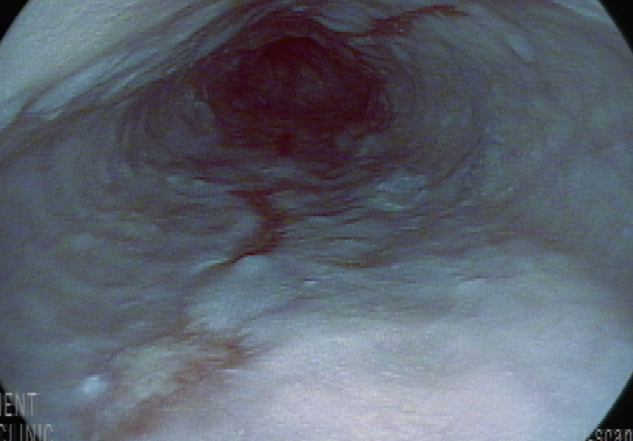

위내시경, LA-B정도의 미란성 식도염 소견

궤양 흔적

헬리코박터 양성 만성 위염